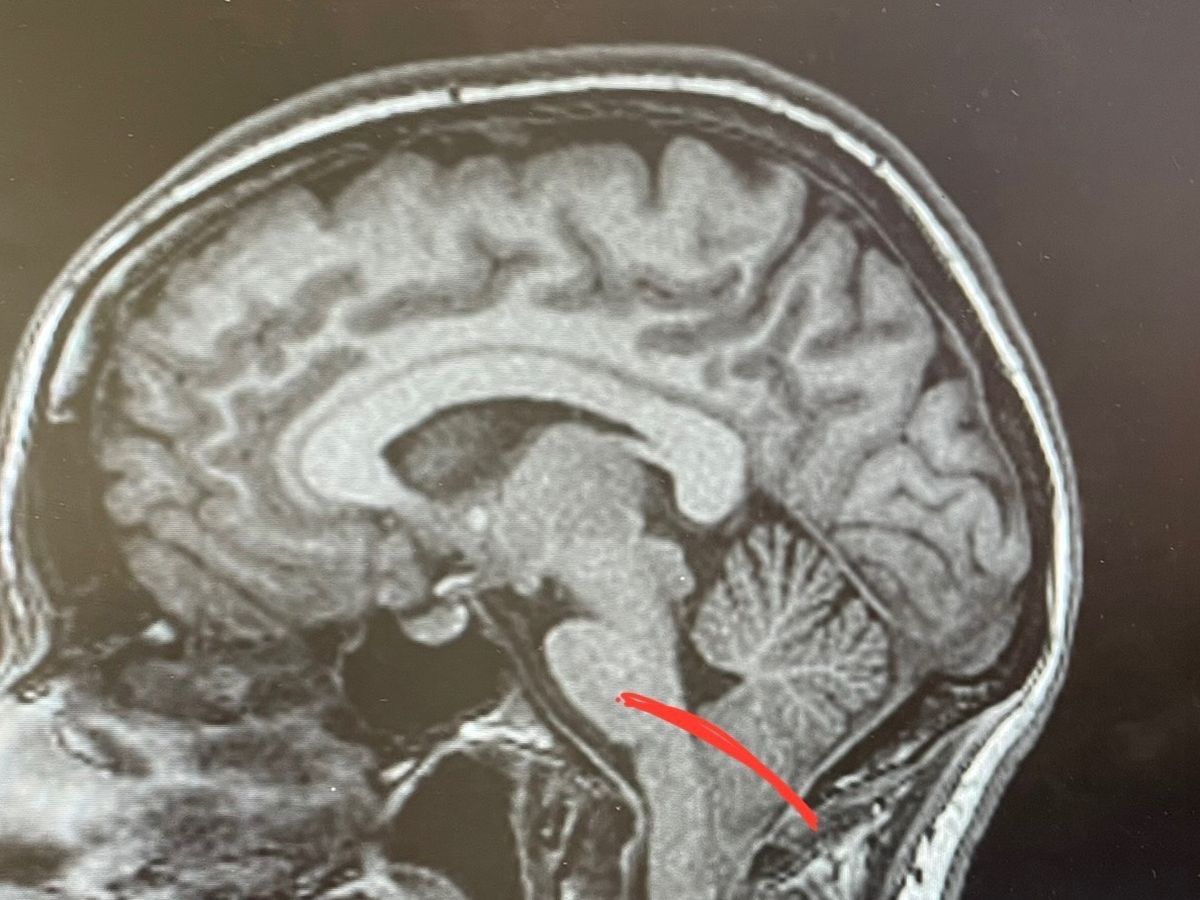

Hello everyone, I will be having brain surgery for a Chiari 1 Malformation on August 7, 2023 (as you can see my brain is massive and way too big for my skull…). I will be out of work and recovering from the procedure for about 3 months. Part of my recovery includes a 3-5 night stay in the ICU/hospital.